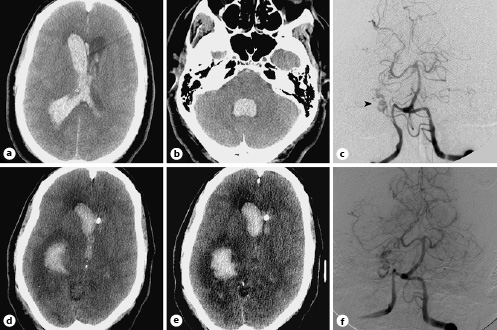

This middle-aged patient presented to the emergency room obtunded. CT of the head (a, b) showed a massive isolated intraventricular hemorrhage within the bilateral lateral ventricles and the fourth ventricle. c Digital subtraction angiogram (DSA) of the left vertebral artery on postbleed day 7 shows vasospasm of the V4 segment of the right vertebral artery and the basilar artery, as well as the P2-P4 segments of both posterior cerebral arteries (PCA). Note the arteriovenous malformation (AVM) nidus and draining vein (arrowhead) drawing supply from the posterior temporal branch of the right PCA. d, e CT of the head on postbleed day 8 shows new areas of hypodensity and loss of grey-white differentiation in the bilateral occipital lobes. f Follow-up DSA 7 weeks after the hemorrhage shows resolution of the vasospasm, as well as improved opacification of the AVM nidus. The patient underwent a successful n-butyl cyanoacrylate (Codman, Raynham, MA, USA) embolization of the AVM.